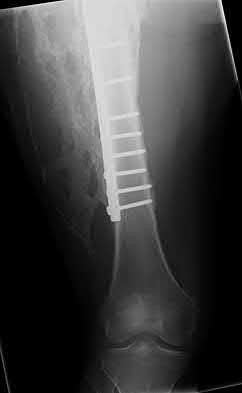

1. # A 32-year-old male sustains the injury shown in Figure A and undergoes treatment as shown in Figure B. Following placement of this implant, what is the best technique to confirm it is not too proud proximally?

1. Lateral radiograph of the knee

The safe zone for tibial nail placement as seen on radiographs is just medial to the lateral tibial spine on the anteroposterior radiograph and immediately adjacent and anterior to the articular surface as visualized on the lateral radiograph.

Tornetta et al specifically located the safe zone for nail entry in a study using fresh frozen cadaver knees. The authors found that the safe zone for nail placement is located 9.1+/-5 millimeters lateral to the midline of the plateau and three millimeters lateral to the center of the tibial tubercle. The width of the safe zone averaged 22.9 millimeters and was as narrow as 12.6 millimeters.

The starting point of the of the nail can be best viewed on the lateral knee radiograph, an example of which is shown in Illustration A. Illustration B shows the "sweet spot" for nail insertion as defined by Tornetta.